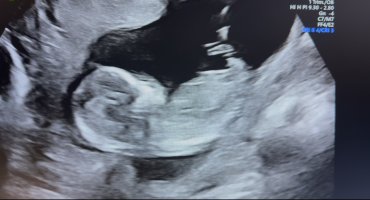

Er du gravid igjen? Sååå kjektNoen som ser noe her? 12+6![]()

Hun er såå spent på kjønnet og spurte om jeg ville legge ut ser ut som jenteNoen som ser noe her? 12+6![]()

JenteNoen som vil gjette her? uke 13+1Vis vedlegget 472328

Tipper også jenteNoen som vil gjette her? uke 13+1Vis vedlegget 472328